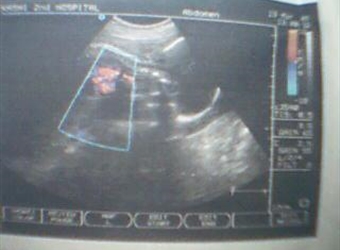

孕妈妈们你知道怀孕七个月时胎儿发育成什么模样了吗?怀孕七个月胎儿图你看过吗?想了解怀孕七个月的胎儿有多大了? 此时胎儿正长在妈妈肚子里的什么位置上面…

怀孕7个月胎儿多大了?想了解怀孕七个月胎儿图是什么样子这个问题恐怕我们只有通过四维彩超才能看得到。您可以通过我院四维彩超看到怀孕七个月胎儿图,我院四…